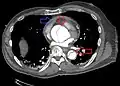

Computed tomography

Computed tomography angiography is a fast, non-invasive test that gives an accurate three-dimensional view of the aorta. These images are produced by taking rapid, thin-cut slices of the chest and abdomen, and combining them in the computer to create cross-sectional slices. To delineate the aorta to the accuracy necessary to make the proper diagnosis, an iodinated contrast material is injected into a peripheral vein. Contrast is injected and the scan performed using a bolus tracking method. This type of scan is timed to injection to capture the contrast as it enters the aorta. The scan then follows the contrast as it flows through the vessel. It has a sensitivity of 96 to 100% and a specificity of 96 to 100%. Disadvantages include the need for iodinated contrast material and the inability to diagnose the site of the intimal tear.